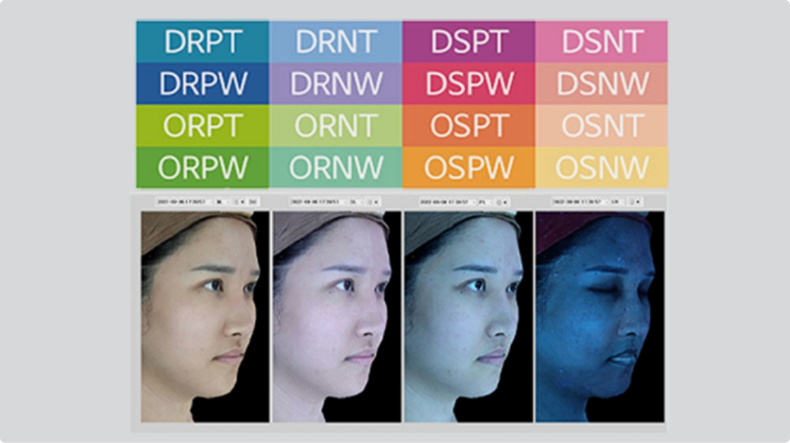

Feature 03

고압산소

치료 원리

고압산소 치료

시술부위